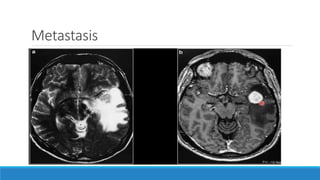

Metastasis